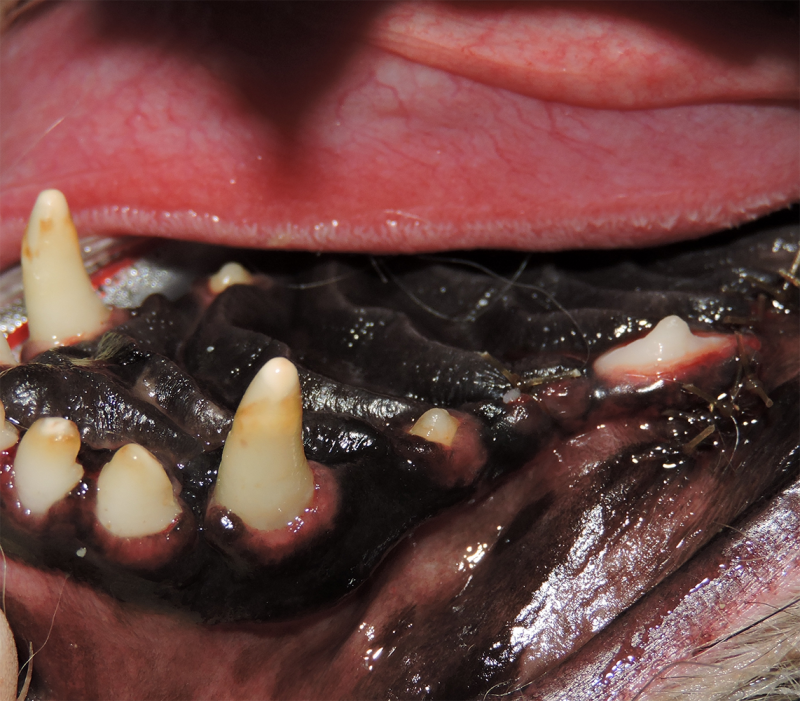

Surgical Extraction of Diseased Teeth

Periodontal disease is extremely common in dogs and cats. Over 80% of dogs and cats over two years of age have some degree of periodontal disease. Periodontal disease is best prevented by yearly professional dental cleanings starting at two years of age and at home brushing at least three times weekly. Brushing should begin at a very early age to allow your new pet to get used to regular brushing. In severe cases of infection or periodontal disease, the teeth may need to be surgically extracted. Extractions should always involve x-rays of the tooth first, as many teeth have multiple roots or may be diseased below where the eye can see. Extracting larger teeth in animals requires oral surgery, equivalent to removing wisdom teeth in people. It is vital that all of the tooth and roots be removed for the periodontal infection to resolve. In cases of important teeth with mild to moderate periodontal disease, multiple periodontal treatments can be offered to help save these teeth.